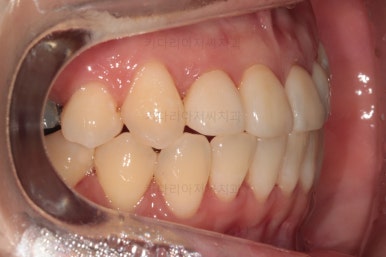

치열은 매우 가지런해졌고요.

추후에 발치 공간을 모아나가야 합니다.

윗니 앞니는 급한대로 신경치료 부터 진행했고, 최종 심미보철은 교정 후 미루었습니다.

공간을 줄여나가고 순차적으로 충치치료도 마무리 해갑니다.

교합이라던가 부족한 부분을 좀 더 마무리하고요.